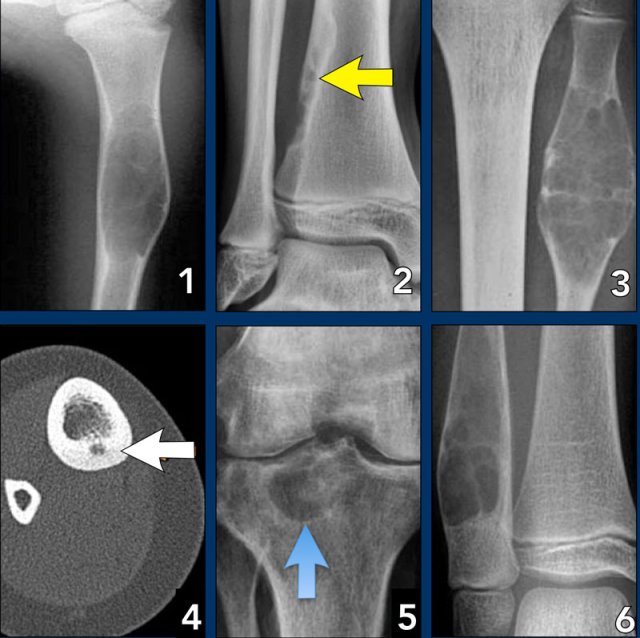

On the left three bone lesions with a narrow zone of transition.

Based on the morphology and the age of the patients, these lesions are benign.

Notice that in all three patients, the growth plates have not yet closed.

Images

- Non-ossifying fibroma

- Solitary bone cyst

- Aneurysmal bone cyst